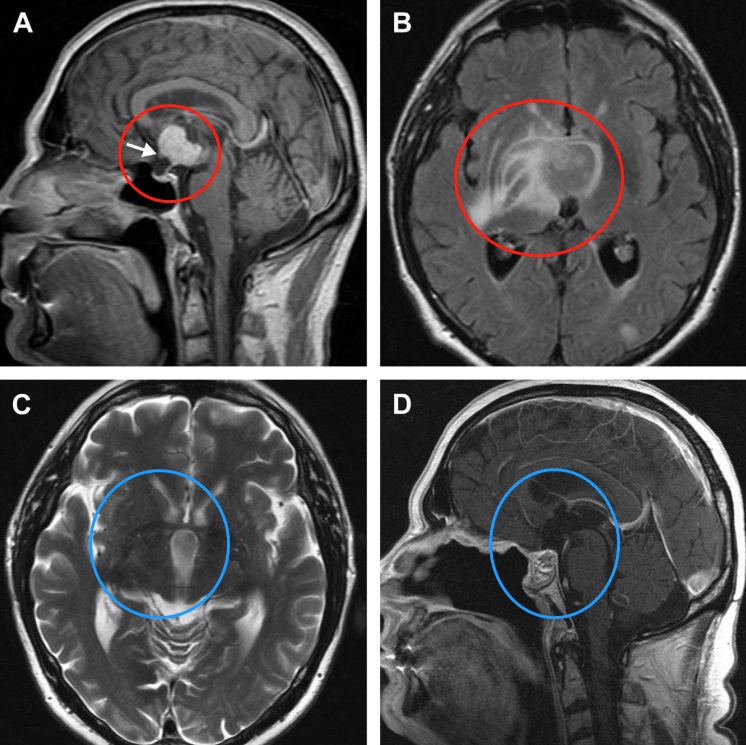

图1后视交叉性较大颅咽管瘤患者肿瘤术前(A,C)和术后(B,D)矢状位增强MR对比,显示肿瘤全切。

INC之德国Henry W.S.Schroeder(施罗德)教授曾在论文中交流了这样一则病例,这位61岁的男性患者有6个月的进行性智力退化史,包括短期记忆减退。入院前10天,患者出现意识障碍、定向障碍及膀胱功能障碍。内分泌学检查显示为尿失禁和尿崩症,有患典型的肾上腺皮质功能减退症Addison病的风险,施罗德教授为其行内镜下颅咽管瘤切除手术。

图14。鞍上增强MRI显示,肿瘤延伸至三脑室,有实性成分(a)。视神经交叉向前移位(箭头)。垂体和蝶鞍似乎正常。由于T2病灶周围水肿和反转恢复图像液体衰减并右侧基底神经节外侧延伸,怀疑下丘脑侵犯(B)。施罗德教授在内镜下行全切术,包括已被肿瘤浸润损害的部分垂体柄。术后2年MRI未见肿瘤复发(C,D)。水肿完全消退(C)。图像(D)也显示鼻中隔皮瓣重建颅底。

术后这名患者经历了短暂的神志不清,但神志及认知功能恢复很快,而且体重保持稳定。需要激素替代。术后两年颅咽管瘤未复发,水肿完全消退。